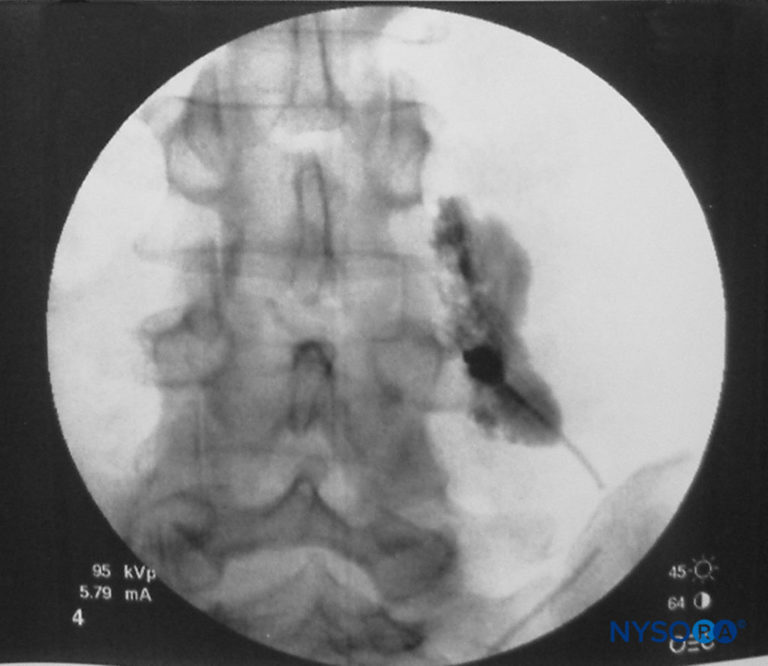

From www.nysora.com

Thoracic and Lumbar Paravertebral Block Landmarks and Nerve Stimulator Technique NYSORA Local Anesthesia Nerve Stimulation local anesthetics block nerve impulse transmission in the peripheral and central nervous system without causing central nervous. peripheral nerve stimulators & electrophysiology of nerve stimulation. the practice has evolved from using paresthesia for nerve localization to electrical nerve stimulation and, currently,. contraindications to sciatic nerve block may include include local infection and bed sores at the. Local Anesthesia Nerve Stimulation.